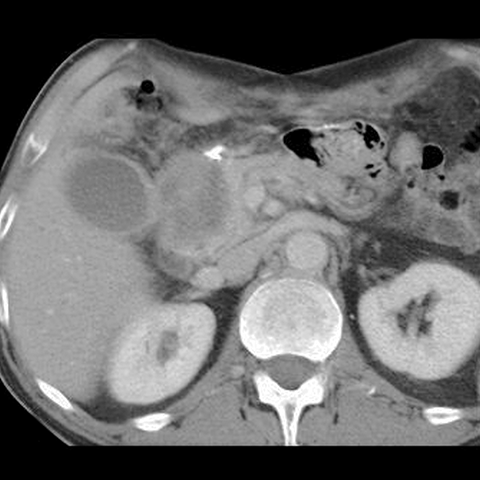

65-year-old male presents with painless jaundice. [3 of 5]